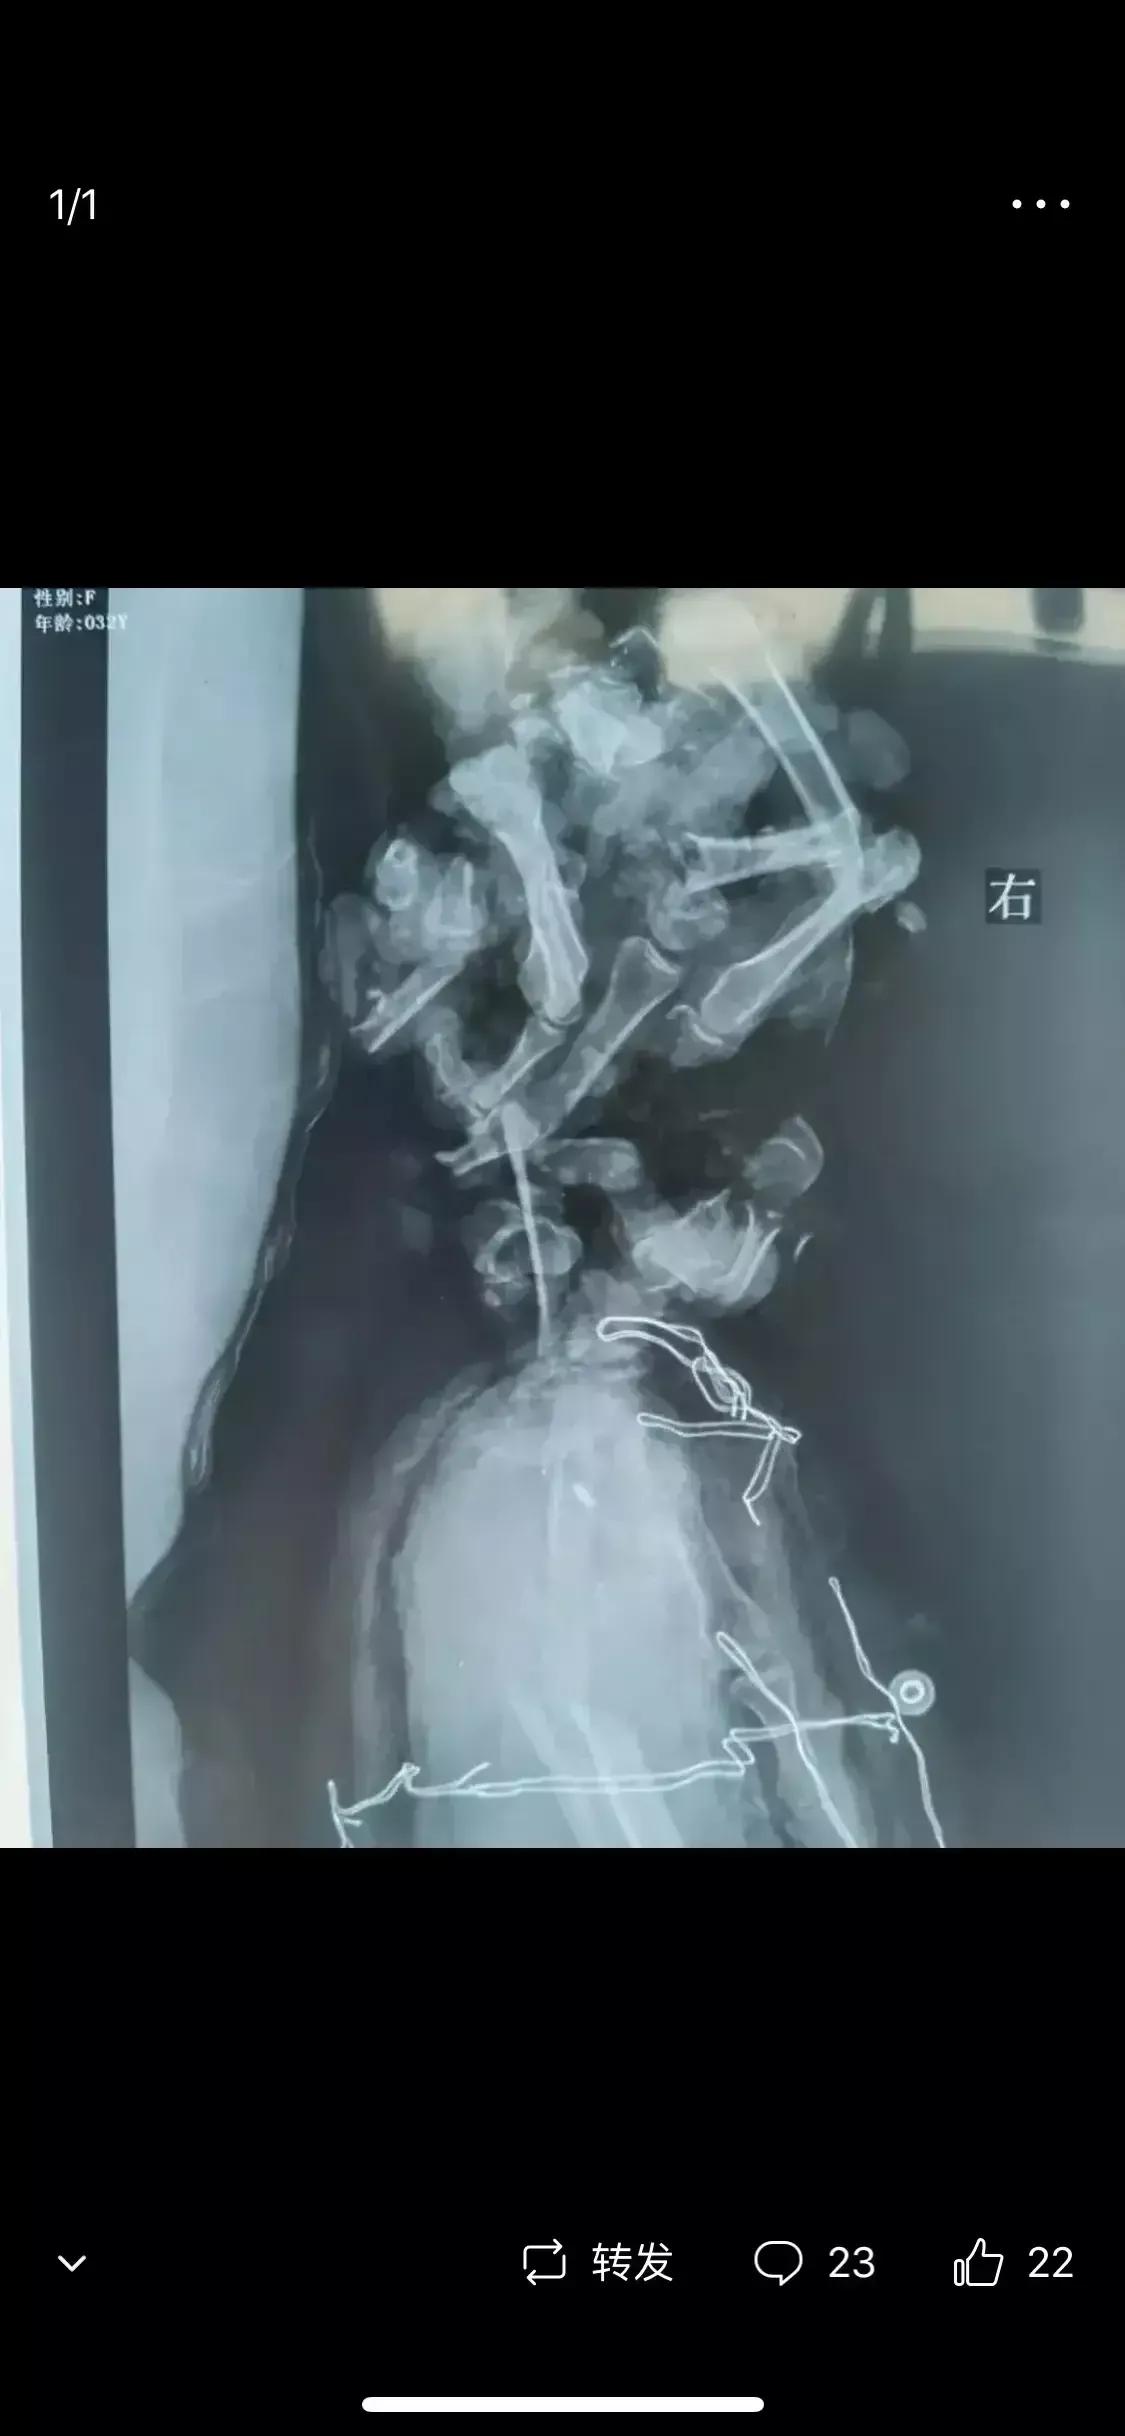

微头条原文:这是今早上看到的一个病例,非常严重的肢端损伤。这在医学上有个名词,叫做毁损伤,就是专门形容这种合并严重骨折,严重软组织挫裂伤,极难修复。

虽然未见软组织损伤的照片,但是其实从片子可以看出是大部离断状态,而且七零八落,功能暂且不论,对于血运就是致命的打击,血运决定了远端肢体是否存活,再来就是最大的风险,感染。